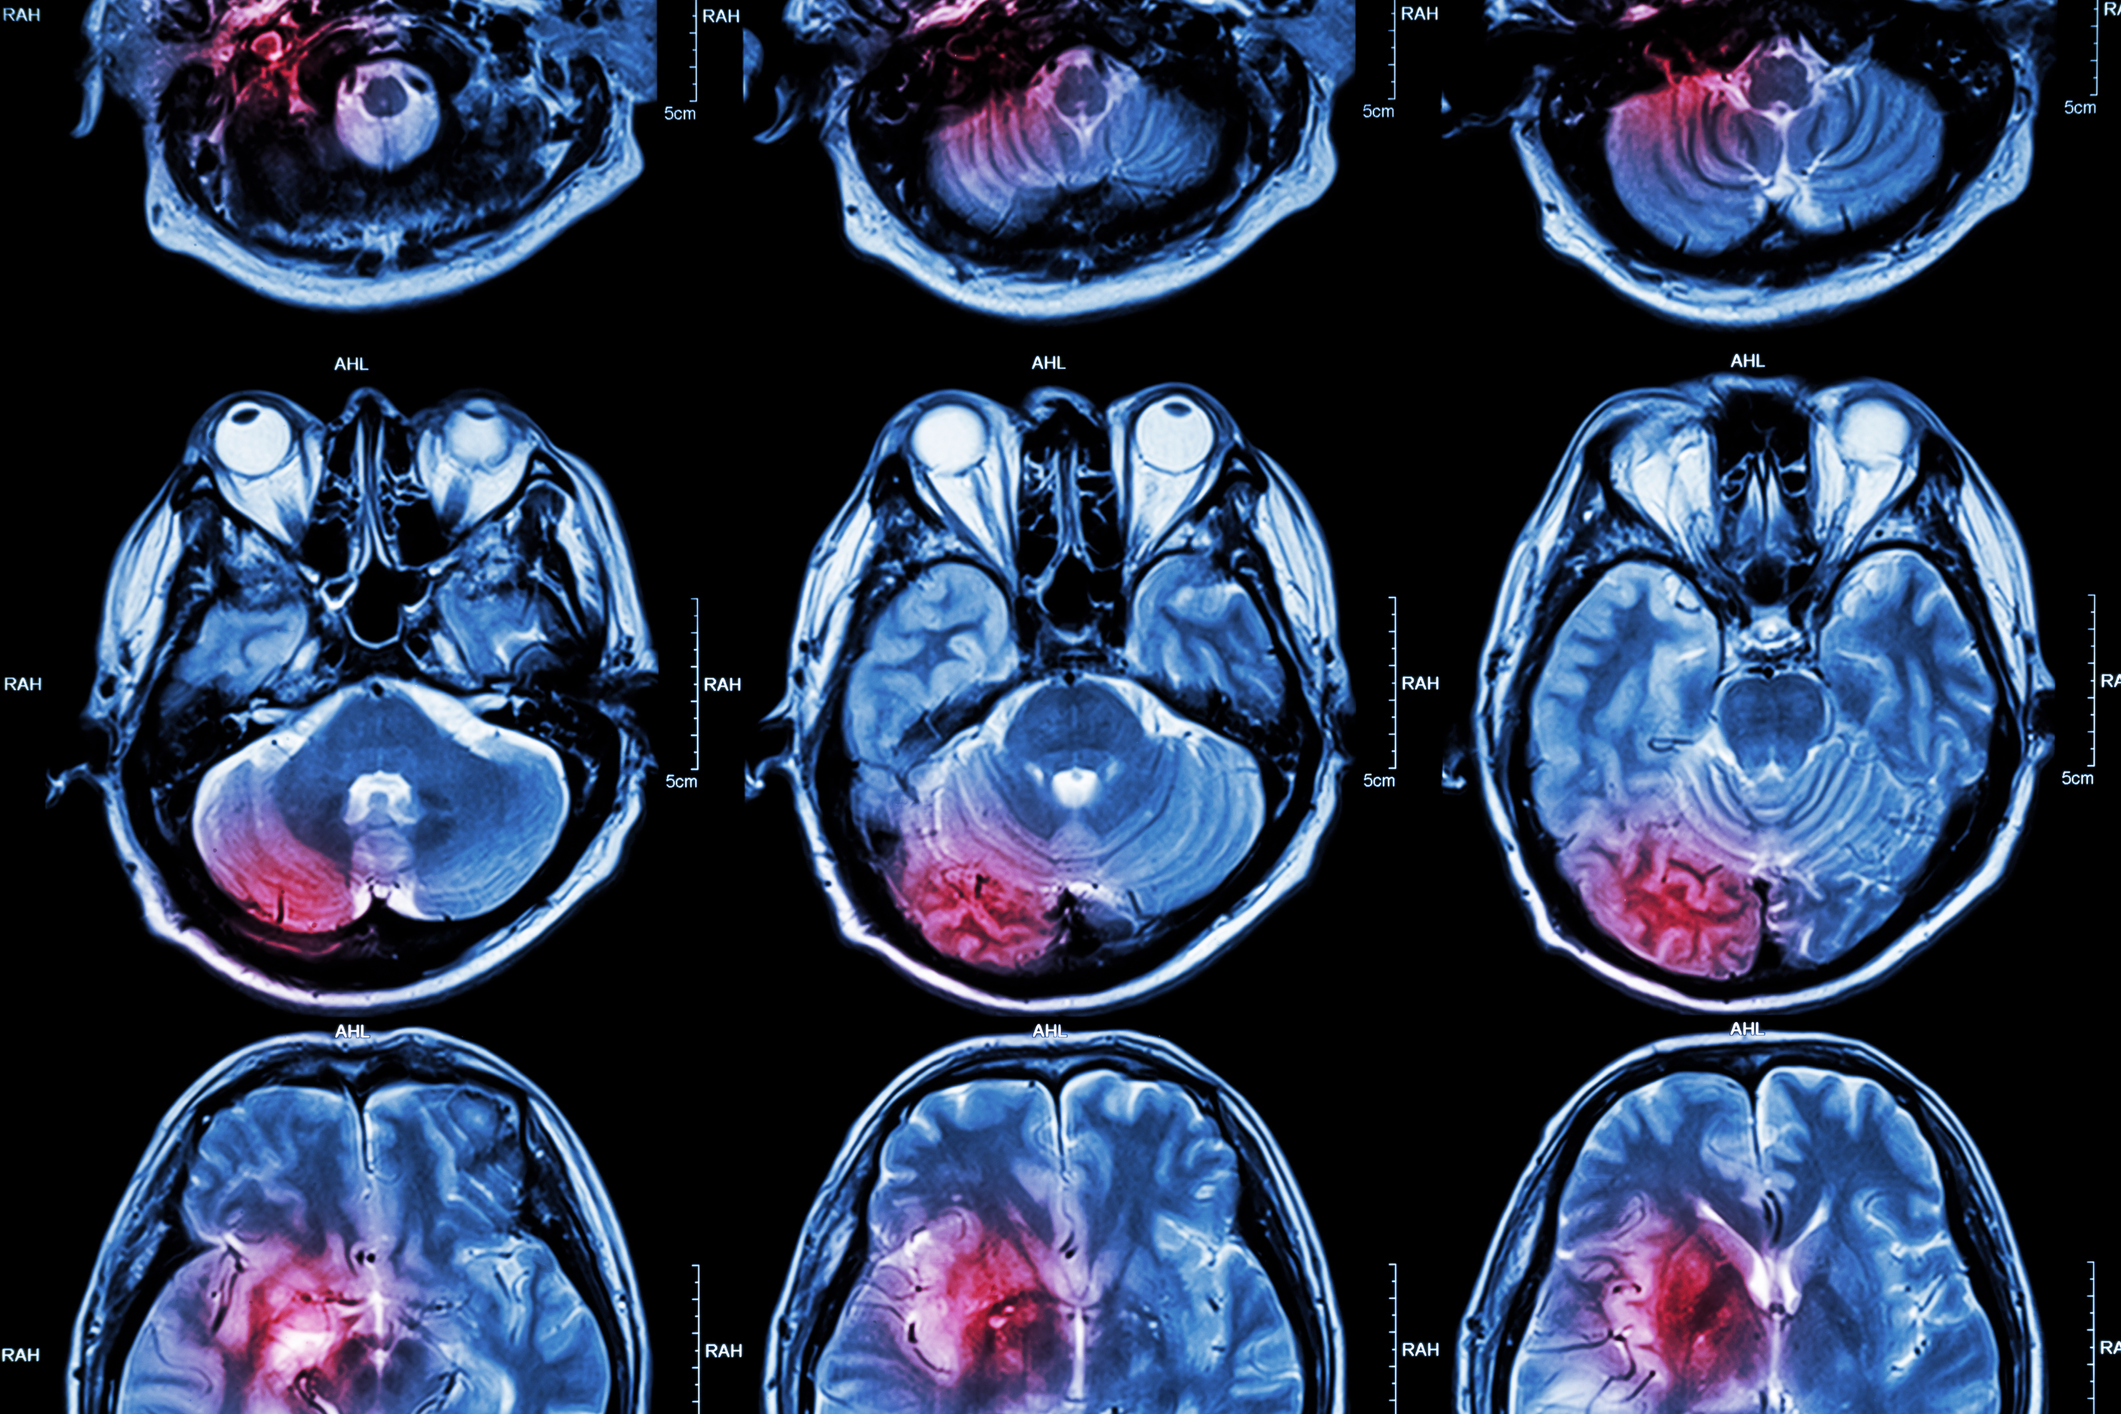

Diffuse Midline Gliomas (DMG), including diffuse intrinsic pontine gliomas (DIPGs) are the most lethal of childhood cancers.

DMGs are a fast-growing tumour forming the part of the brain responsible for life sustaining functions like heartbeat, breathing, swallowing, eyesight, and balance.